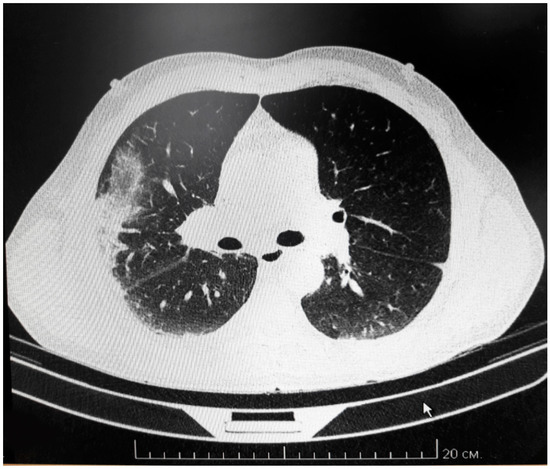

3.1.1. Presentation

3.1.2. Clinical Testing

3.1.3. Treatment

3.1.4. Clinical Diagnosis